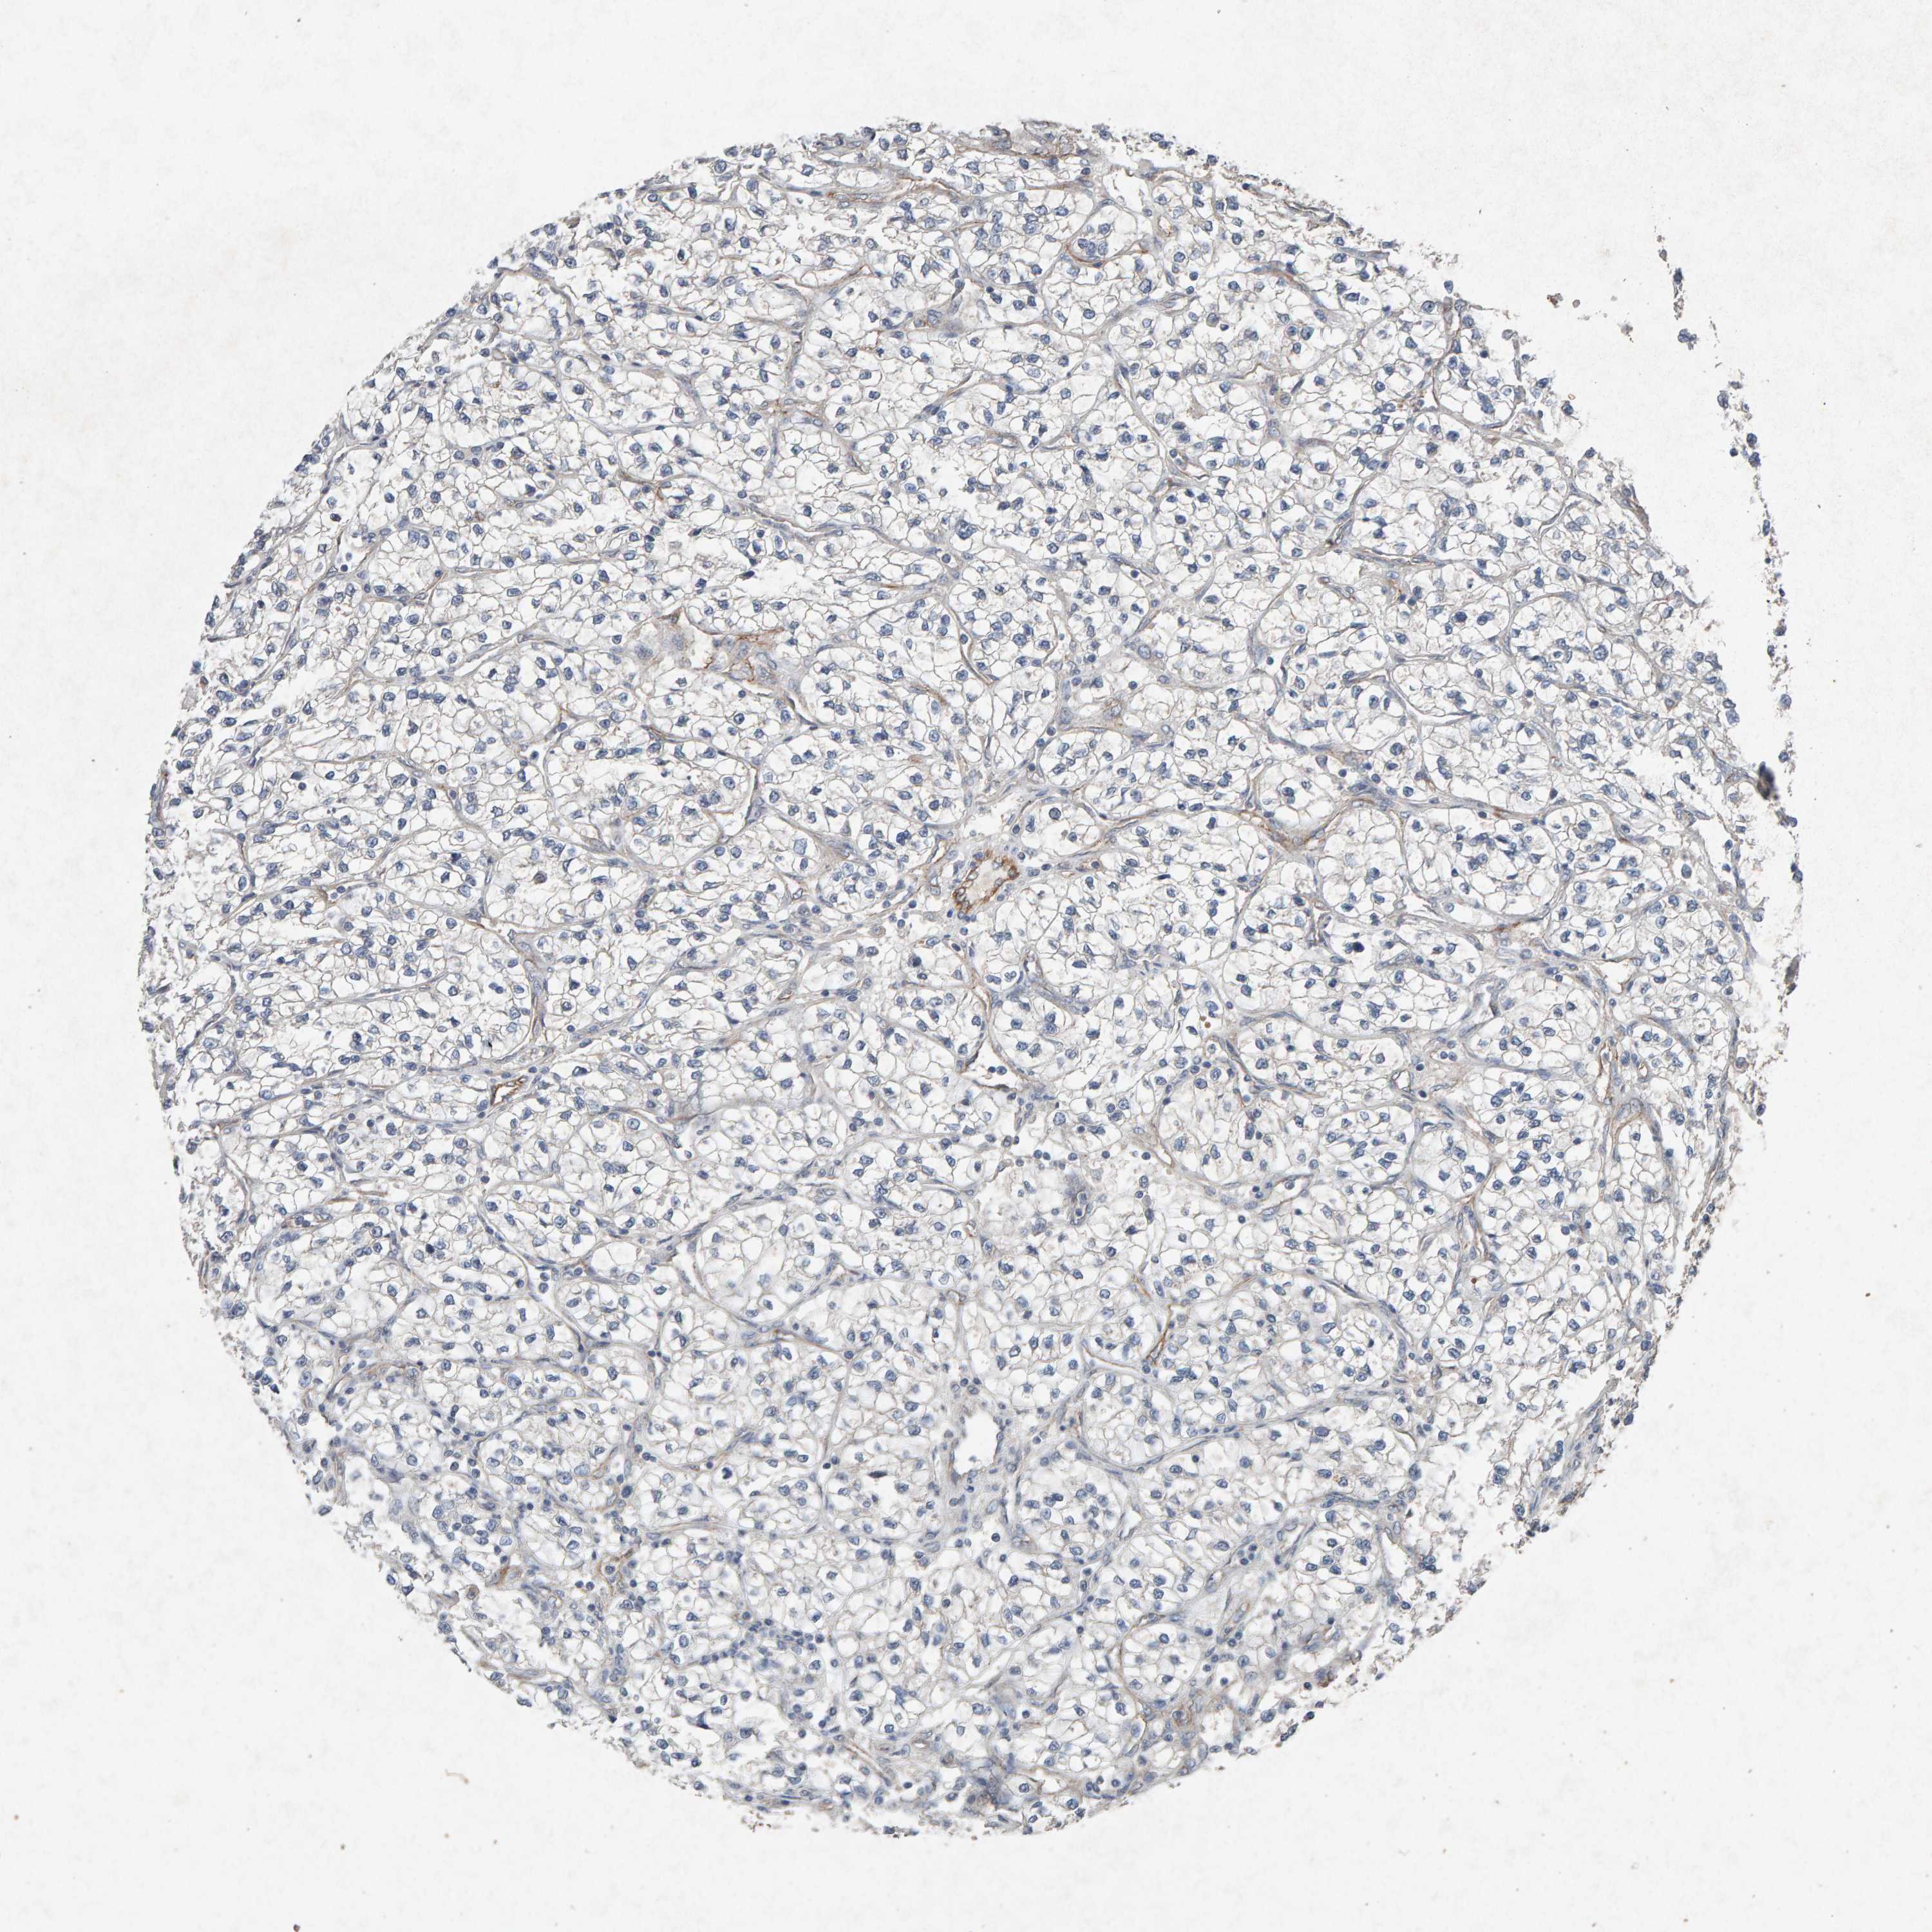

PTPRM is not prognostic in Kidney Chromophobe (TCGA)

Stage:

Survival analysis

: 10.45

Average pTPM 15.0

Number of samples 64